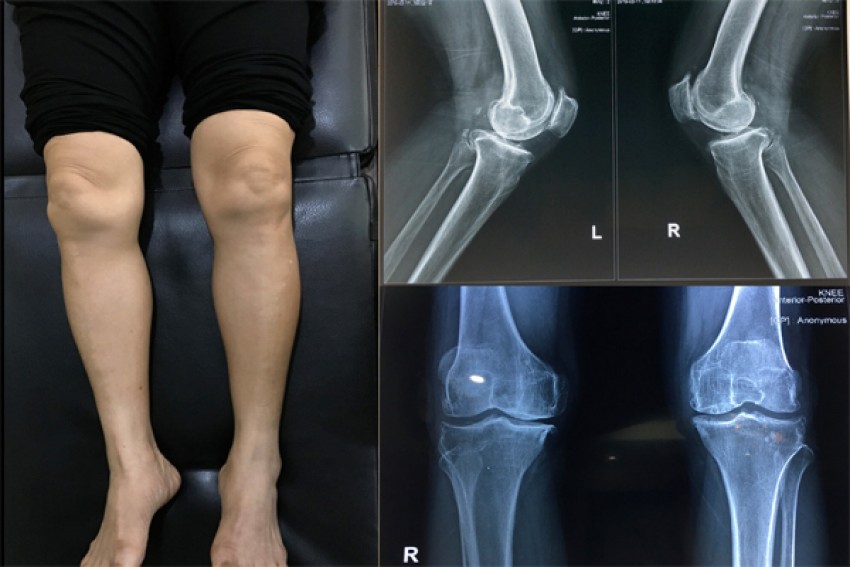

Hình ảnh trên phim chụp Xquang của bệnh thoái hóa khớp gối.